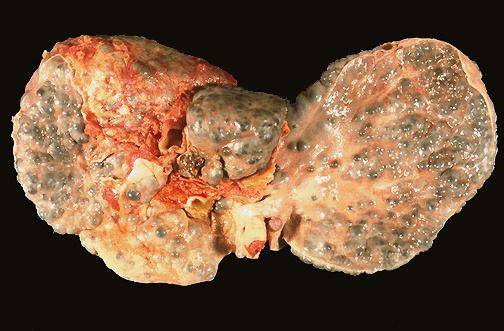

Итак, что представляет собой данный недуг? В первую очередь это нарушение структуры вышеуказанного внутреннего органа человека, которое характеризуется заменой «здоровых» клеток печени рубцовой соединительной тканью. Как следствие, после этого формируется функциональная недостаточность «самой массивной» железы в человеческом организме, и свою работу нормально она выполнять уже не в состоянии.

Так, сам цирроз имеет различные формы, что является основным фактором, определяющим продолжительность жизни пациента:

- Компенсированный цирроз (стадия заболевания, когда оставшиеся здоровые клетки печени могут выполнять свои функции). При такой стадии заболевания, и при соблюдении всех предписаний у пациента есть шанс прожить от семи до десяти и более лет;

- Субкомпенсированный цирроз (стадия заболевания, подразумевающая полное истощение здоровых клеток печени и их отмирание). В этом случае у пациента есть шанс прожить не более шести лет. Однако стоит отметить, что прогноз для каждого пациента в любом случае будет индивидуальным.

- Декомпенсированный цирроз (стадия, характеризующаяся полным отказом органа и последующими осложнениями). В этом случае прогноз для пациента крайне неблагоприятный. Как правило, длительность жизни в этом случае составит не более трех лет.